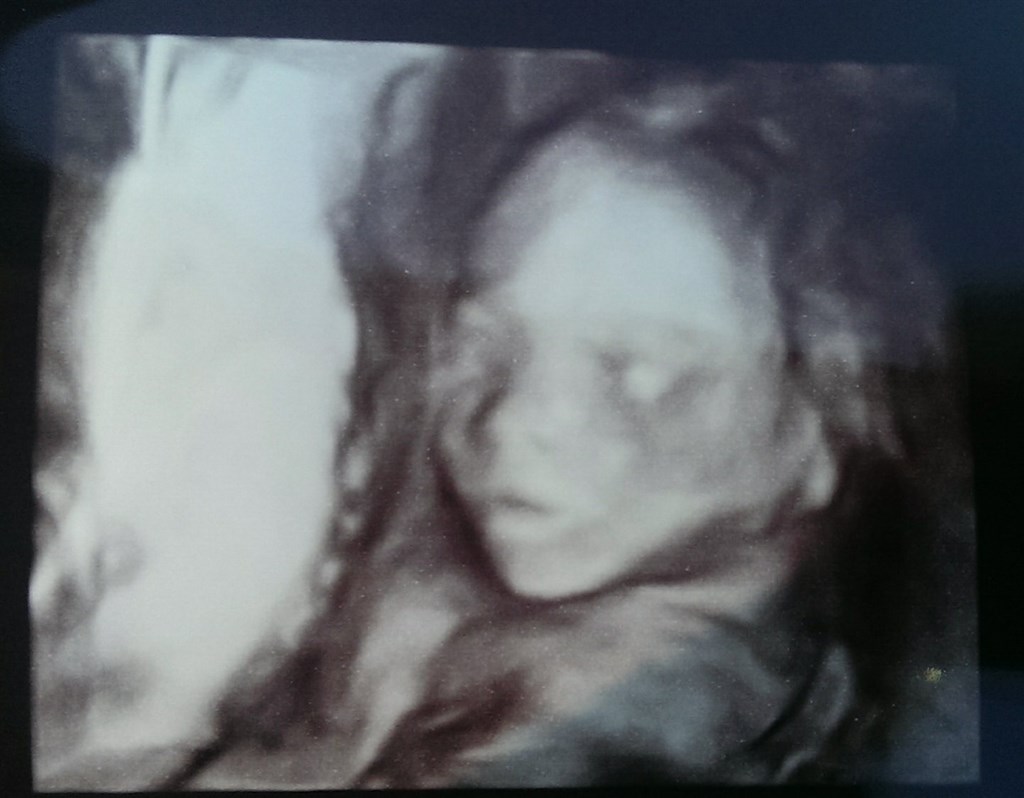

Fandt ud af det var en lille pige inde i maven så er også nogle ting jeg lige skal omstille, da jeg altid har været van til drengebørn. (har passet mange børn, men gik først op for mig at jeg aldrig havde passet piger, før jeg fandt ud af, at det var en pige) Det bliver lidt sjovt.

også lige lidt billeder.